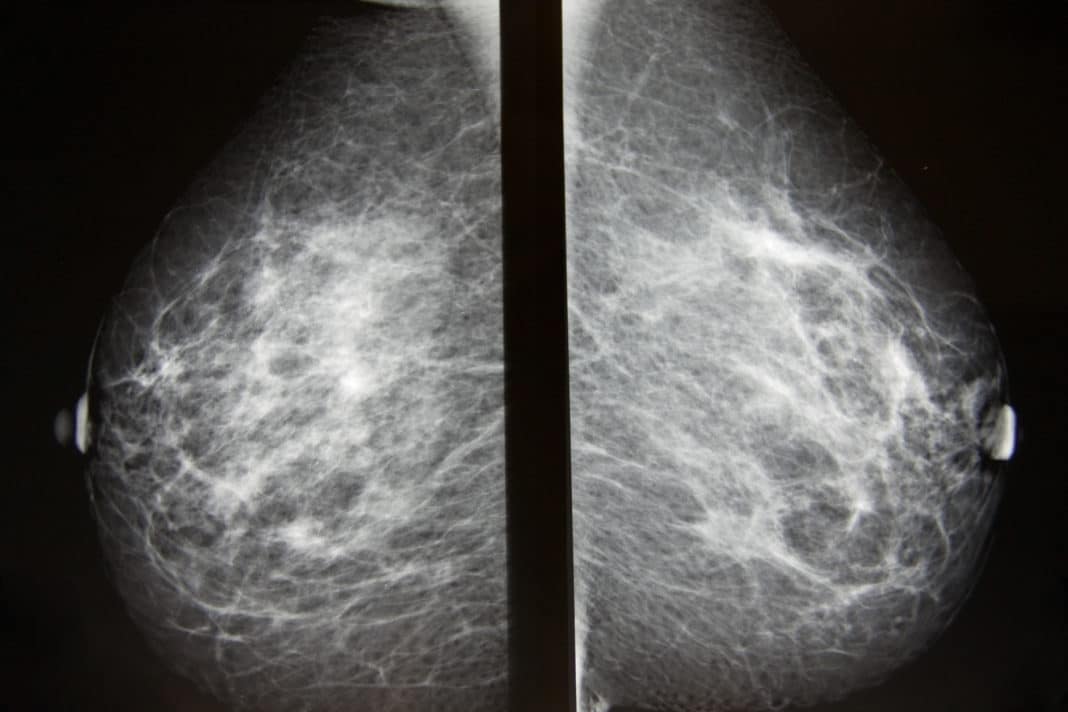

На жаль, незважаючи на всі зусилля вчених, своєчасне діагностування раку молочної залози (РМЗ), так і

Ракових новоутворень грудної залози належить перше місце в структурі жіночої онкопатології.